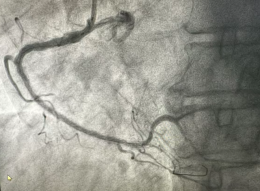

专业守护从“心”开始日照市康复医院心脏康复科今年73岁的于大爷(化名),半月前突发持续性胸痛被紧急送至我院急诊科。检查发现,于大爷患有急性广泛前壁心肌梗死,情况危急。既往有高血压病史4年,血压最高达1...